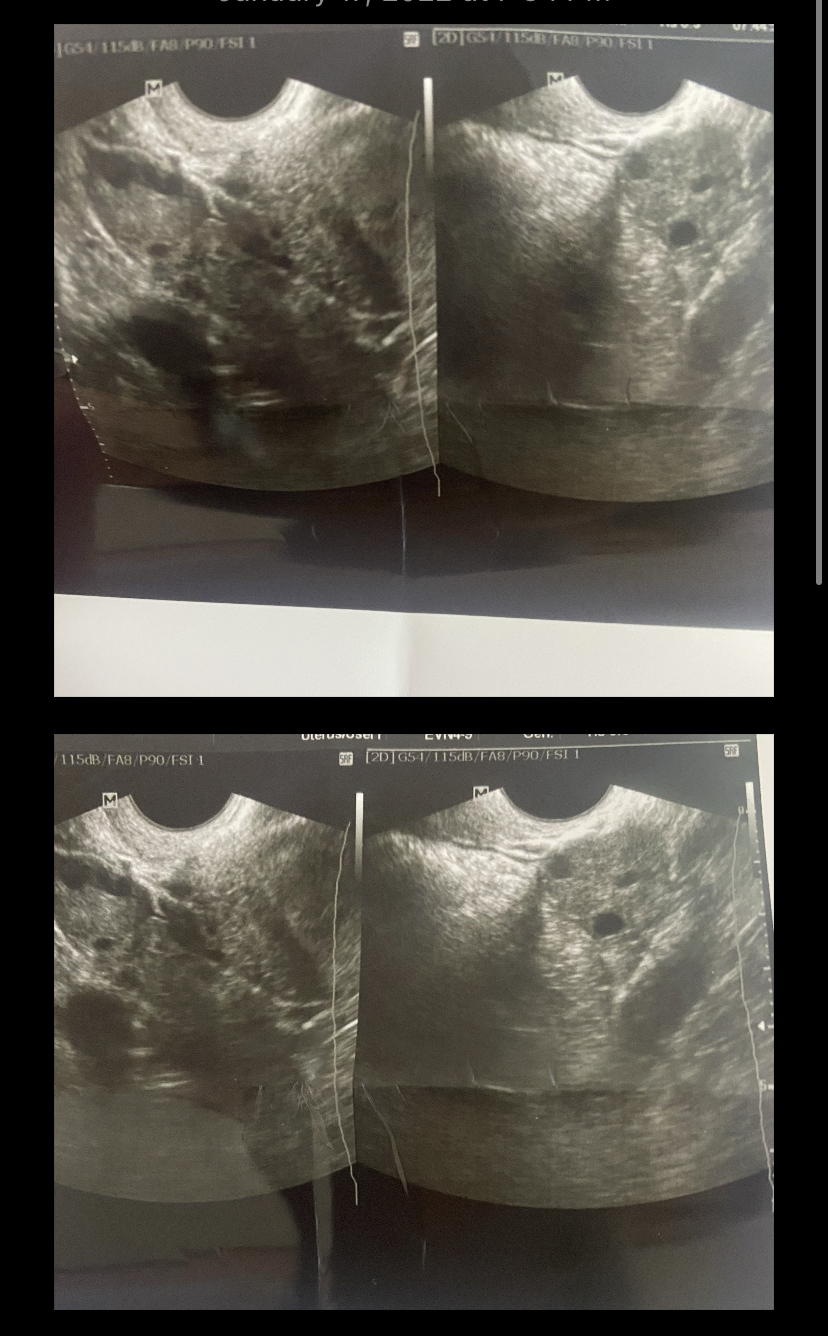

هذي صور الرحم ياريت تقوليلي

رحمي طفولي ونزول الدورة عند اخذ الحبوب ومبايضي ضعيفه لاكن عند اخذ ابر الهرمونيه تصعد نسبة مبايض هل يوجد امل...